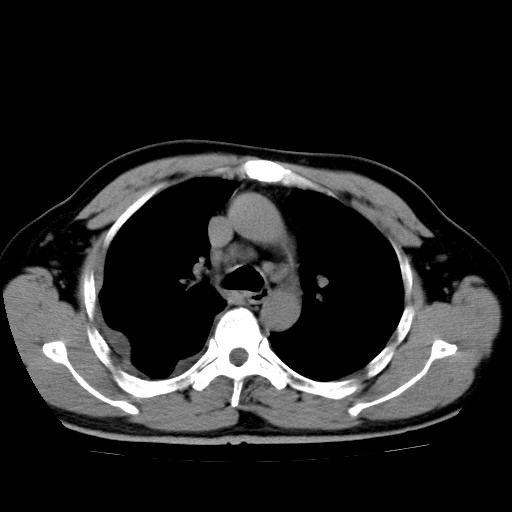

男,54岁,咳嗽,右侧胸痛10天。肺窗>150k,传不了

右肺中心型肺癌并右下肺不张,右侧胸膜纵隔转移。

右中央型肺癌并右肺下叶不张,纵隔内及右胸膜转移,右胸腔积液

考虑   右肺癌伴右下肺部分不张,阻塞性肺炎,纵隔淋巴结增大,右侧胸腔积液其他待排

考虑右肺下叶中央型肺癌并右肺下叶不张,纵隔淋巴结内及右胸膜转移。建议增强。

右下叶大片实变,肺门未见明显肿块影。有胸腔积液和纵隔内肿大淋巴结影。没有增强和肺窗,不好定。

考虑:1、右下叶周围型肺癌伴胸膜、纵隔淋巴转移?